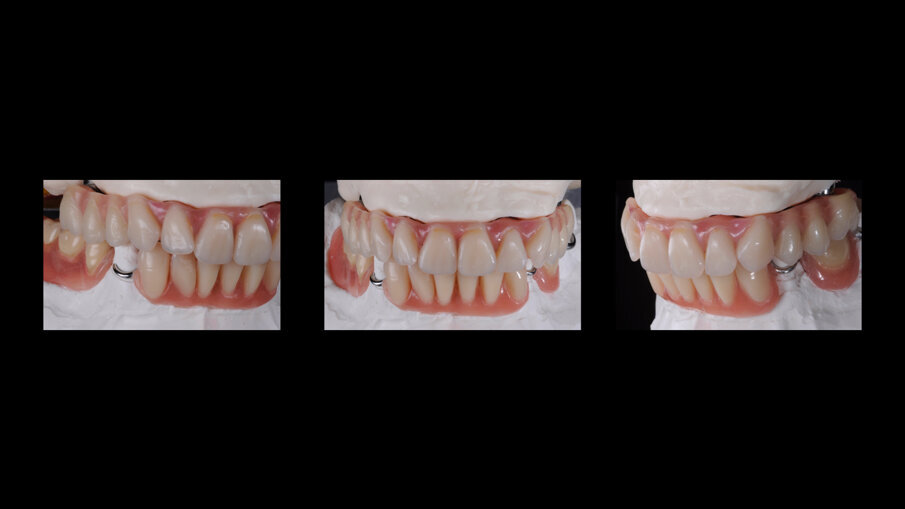

Il primo passo per riabilitare la paziente è stato comunque la sostituzione della protesi totale con una nuova più congrua, questo ha portato alla correzione sia della classe scheletrica non corretta che della VDO, fonte di disagio e sofferenza. L’esame extra-orale evidenziava questo dettaglio e come questo influenzasse il sorriso della paziente (Figg. 5-7).

La nuova protesi totale provvisoria ha portato immediatamente un miglioramento funzionale ed estetico, con un notevole beneficio psicologico sulla paziente ed un enorme vantaggio per il prosieguo della terapia (Figg. 8-10). Il nuovo montaggio con denti di maggiori dimensioni ed una differente occlusione ha conferito un miglior supporto al labbro superiore ed una migliorata estetica del sorriso (Fig. 11). Alla luce della nuova situazione, accettata e gradita dalla paziente, si è incominciato a pianificare la procedura chirurgica. Avendo la CBCT evidenziato dei volumi ossei adeguati (Fig. 12), si è proceduto allo studio del caso mediante un software di chirurgia guidata (Simplant, Dentsply-Sirona) (Figg. 13, 14).